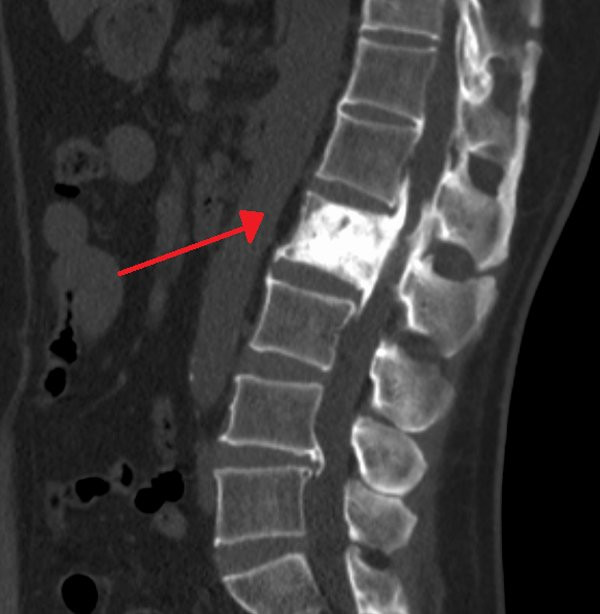

Hình ảnh chụp X-quang xương của một bệnh nhân mắc bệnh Paget.